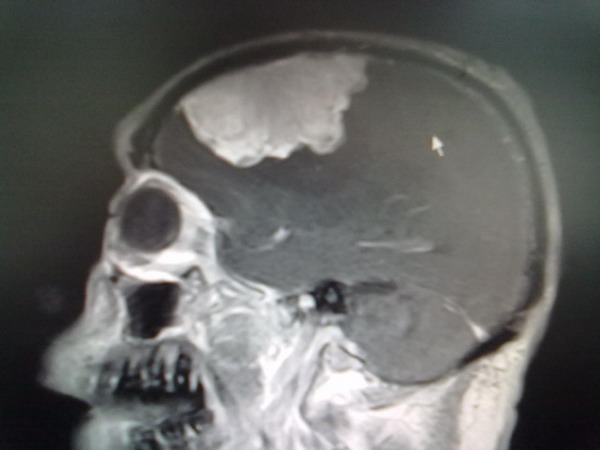

患者罗某,男,57岁。因“右侧肢体无力3年,行走不能并言语错乱1个月”于2013年1月29日由骨关节创伤科转入外六科。患者于3年前始,不明原因下出现右侧肢体无力,逐渐加重,一个多月前因肢体乏力摔倒致“右股骨粗隆间粉碎性骨折,右股骨头缺血性坏死,并右髋关节脱位”收入创伤骨科。入院后为查明肢体乏力及言语错乱原因,行头颅磁共振检查示:左侧额颞顶区矢状窦傍巨大脑膜瘤。经会诊后转入外六科。转入时检查见患者神志模糊,言语错乱,答非所问,记忆力及定向力差,体格极度消瘦;右侧肢体肌力差,右髋部压痛,右髋关节活动受限,右下肢肌萎缩,病理征阳性。

经该科术前讨论和分析,患者诊断明确,左侧额颞顶区矢状窦傍巨大脑膜瘤是引起患者右侧肢体无力并摔倒骨折的原因,而且肿瘤巨大,左大脑半球被严重挤压,周围水肿明显,随时引起脑疝死亡,应先行脑部肿瘤手术挽救患者生命,再治疗骨折。但肿瘤巨大,约8cm×6cm×6cm,几乎占左侧大脑半球的一半,且血供异常丰富。而且患者由于长期大量饮酒,存在肝功能不同程度损害,营养较差、体格消瘦,手术耐受力欠佳,若术中如出现大出血,有可能危及生命。因此,以张高炼为主刀的手术组医师制定出最佳的手术治疗方案,术前作了充分准备。

术前影像学改变